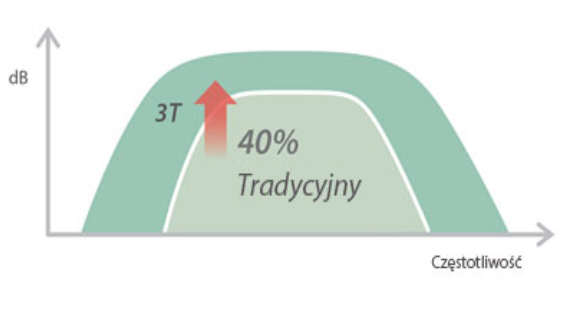

X-Insight to rozwi?zanie umo?liwiaj?ce wnikliw? analiz?, zapewniaj?c bardziej szczeg├│?owy obraz.

Opieraj?c si? na analizie potrzeb klienta, DC-60 Exp X-Insight zosta? zaprojektowany tak, aby znacznie usprawni? diagnostyk?, kt├│ra jest wspomagana przez technologi? eXpress Clarity, eXceptional Intelligence i eXceeding Experience.